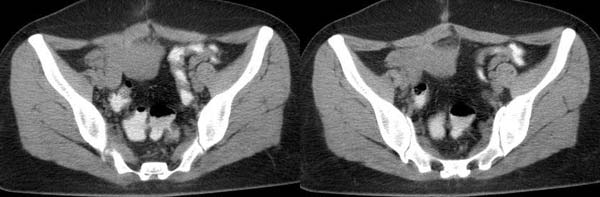

以下是引用守望可可西里在2006-7-25 19:56:00的发言:[br][br] 尽管极象妊娠囊,但“胎儿骨骼12周以后才会在x线片上显影 ,16周以上才可以清晰显示 。一般胎儿的脊柱先出现骨化 ,呈串珠样排列的小点状致密影” 再加上囊内应该是羊水的位置被脂肪密度所取代,还是先考虑畸胎瘤吧。

以下是引用hanlongjiang在2006-7-27 8:24:00的发言:[br]临床手术结果右侧巢畸胎瘤,左侧宫外孕,手术前宫外孕破裂,故手术非常成功,此病例仅凭片子的诊断不能解释其临床表现。想给大家看看,谢谢各位楼主![br]